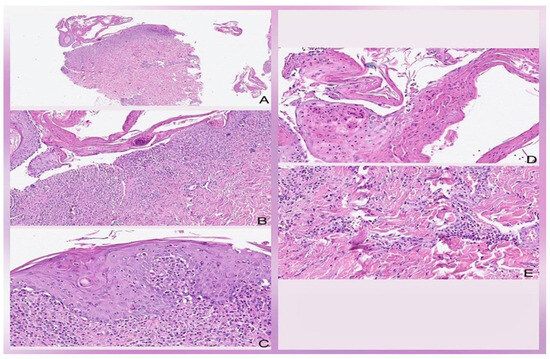

DRESS and Stevens–Johnson Syndrome Overlap Secondary to Allopurinol in a 50-Year-Old Man—A Diagnostic and Treatment Challenge: Case Report

by José Dario Martínez, Rodolfo Franco, Luis Manuel Sáenz, Americo Guadalupe Alvarado, José Antonio García, Sergio Máximo Delgado, Marius-Anton Ionescu, Camelia Busilă and Alin Laurentiu Tatu

Life 2023, 13(12), 2251; https://doi.org/10.3390/life13122251 - 24 Nov 2023

Drug reaction with eosinophilia and systemic symptoms (DRESS) syndrome is a drug reaction commonly related to eosinophilia, from uncertain epidemiology, and without consensus for diagnosis and treatment globally. It presents a great challenge in its management and is characterized by fever, lymphadenopathy, skin [...] Read more.

Drug reaction with eosinophilia and systemic symptoms (DRESS) syndrome is a drug reaction commonly related to eosinophilia, from uncertain epidemiology, and without consensus for diagnosis and treatment globally. It presents a great challenge in its management and is characterized by fever, lymphadenopathy, skin rash, and multisystemic involvement. An aggressive and difficult-to-manage clinical case is presented in a 50-year-old man with chronic kidney disease due to diabetes mellitus type 2 and systemic arterial hypertension, who developed an unusual variant similar to DRESS and Stevens–Johnson syndrome (SJS) overlap secondary to allopurinol, with skin manifestations without eosinophilia, but fulfilling clinical and laboratory criteria for DRESS and SJS syndrome. Full article